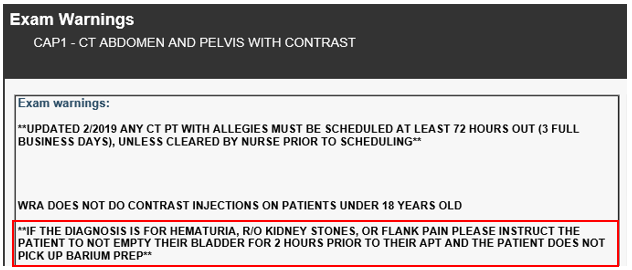

- NOTE: This information is also available on the CT Exam Warning that populates just before the Questionnaire...

- Patient is scheduling a CT Abdomen & Pelvic WITH Contrast and the reason for the exam is hematuria and flank pain...